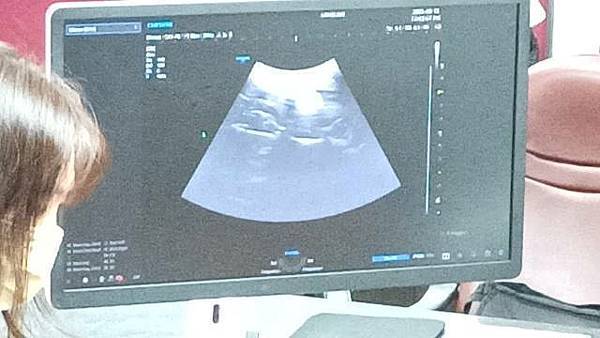

衛福部臺南醫院林語涵醫師表示,射頻消融技術(RFA)是一種超微創手術技術,旨在透過高頻無線電波,將特殊設計的射頻針在超音波或內視鏡導引下插入子宮肌瘤或肌腺症患部,射頻電波會讓組織內帶電離子震動自行產生熱能,因而消除或縮小病變組織。